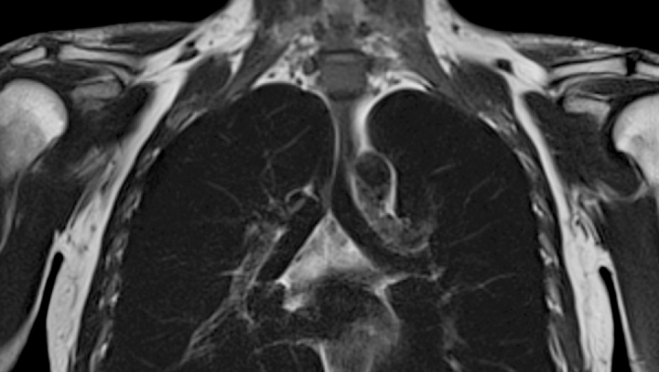

Информация стала известна благодаря исследованию результатов компьютерной томографии пассажиров лайнера Diamond Princess, заразившихся COVID-19. Всего на корабле было инфицировано 104 человека, у 76 из них вирус никак не проявлялся. При изучении топографий уже у 41 человека с положительными тестами на коронавирус, но без проявлений болезни найдены изменения в лёгких – «эффект матового стекла».

В связи с данными исследованиями, учёные сделали вывод о том, что вирус поражает лёгкие в независимости от наличия симптомов.